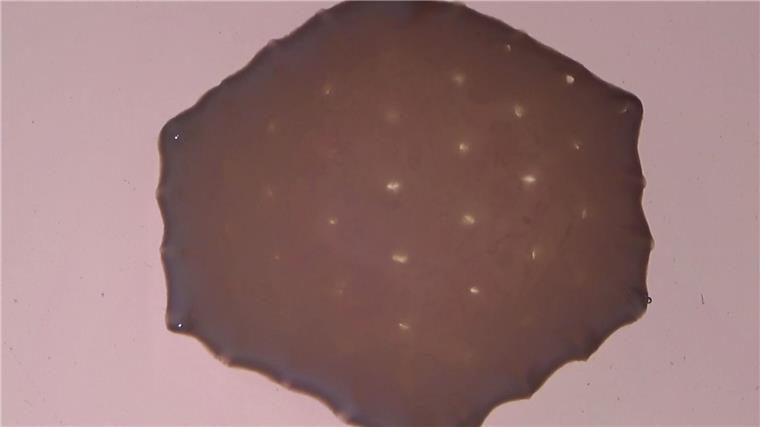

Für das „Herzpflaster“ wird aus den iPS-Zellen Herzmuskelgewebe gezüchtet, das sowohl Herzmuskelzellen enthält als auch Bindegewebszellen. Die Herstellung dauert laut Zimmermann etwa drei Monate. Das aus mehreren Teilen zusammengesetzte und nach Forscherangaben etwa 100 Kubikzentimeter große Implantat wird auf den geschwächten Herzmuskel aufgebracht und soll die Pumpleistung dauerhaft erhöhen.

Die Teile des „Herzpflasters“ werden im Labor gezüchtet.